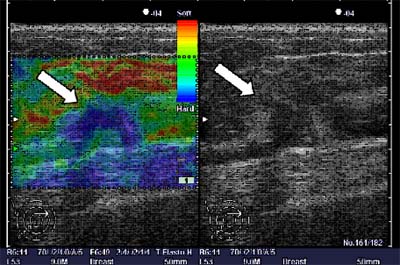

Tale metodica di recente presentata a livello mondiale va inserita in un esame ecografico completo che utilizzi quindi tutte le metodiche a disposizione e sonde ad elevata frequenza 13-15 MHz per raggiungere una corretta diagnosi (il color Doppler, il power Doppler, ove indicato il mezzo di contrasto) e permette di fare una ecopalpazione: di avere informazioni sulle caratteristiche elastiche del tessuto in esame (figura 1).

Al momento tale applicazione trova indicazione nello studio delle nodularità mammarie delle quali permette di conoscere le proprietà meccaniche (elastiche) e quindi l’eventuale rigidità del tessuto permettendo una caratterizzazione tissutale che nel caso della maggioranza della patologia nodulare maligna appare configurarsi come più “rigida” (figura 2).